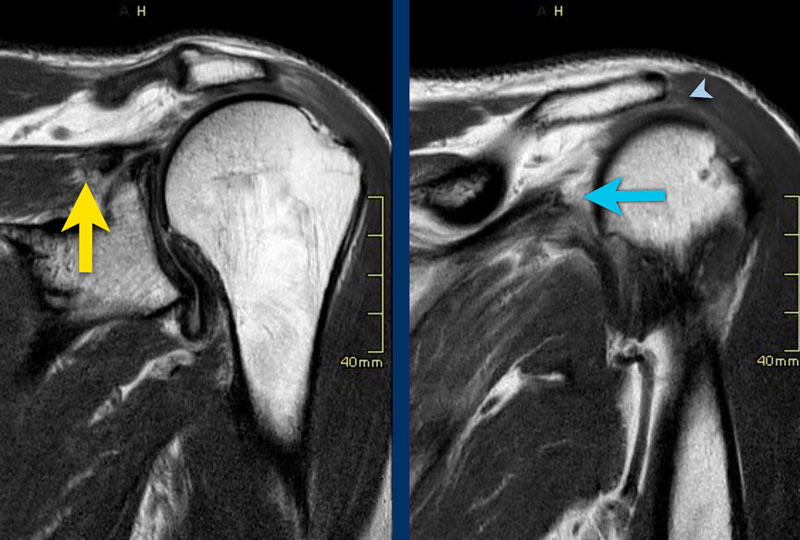

Preoperative MRI of a right shoulder demonstrating cuff tear Rotator Cuff Tear Arthropathy Of Right Shoulder   what is a rotator cuff tear?   rotator cuff arthropathy is a specific pattern of shoulder degenerative joint disease that results from a rotator.   the purpose of this article is to review the biomechanical properties of the rotator cuff and glenohumeral joint and the pathophysiology,. Identify the risks and physical exam findings associated with a complete rotator cuff. Rotator Cuff Tear Arthropathy Of Right Shoulder.